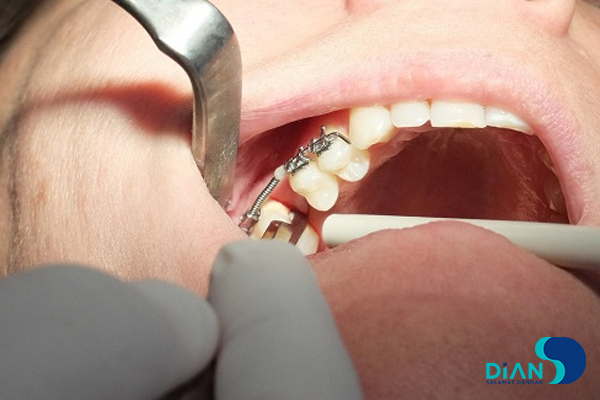

The experienced dentist Dr. Müesser Aktaş from Turkey successfully performed a dental implant procedure using Bio3 Implants in the molar region. For this operation, Dr. Aktaş utilized the Bio3 surgical kit, which is specifically designed to provide precision, ease of use, and efficiency during implant placement. The system’s user-friendly design and reliable components allowed for a smooth and accurate procedure, ensuring optimal results for both the patient and the clinician. This case once again highlights the practicality and advanced engineering of Bio3 Implants, making them a trusted choice for dental professionals worldwide.

Implantation in Molar Area